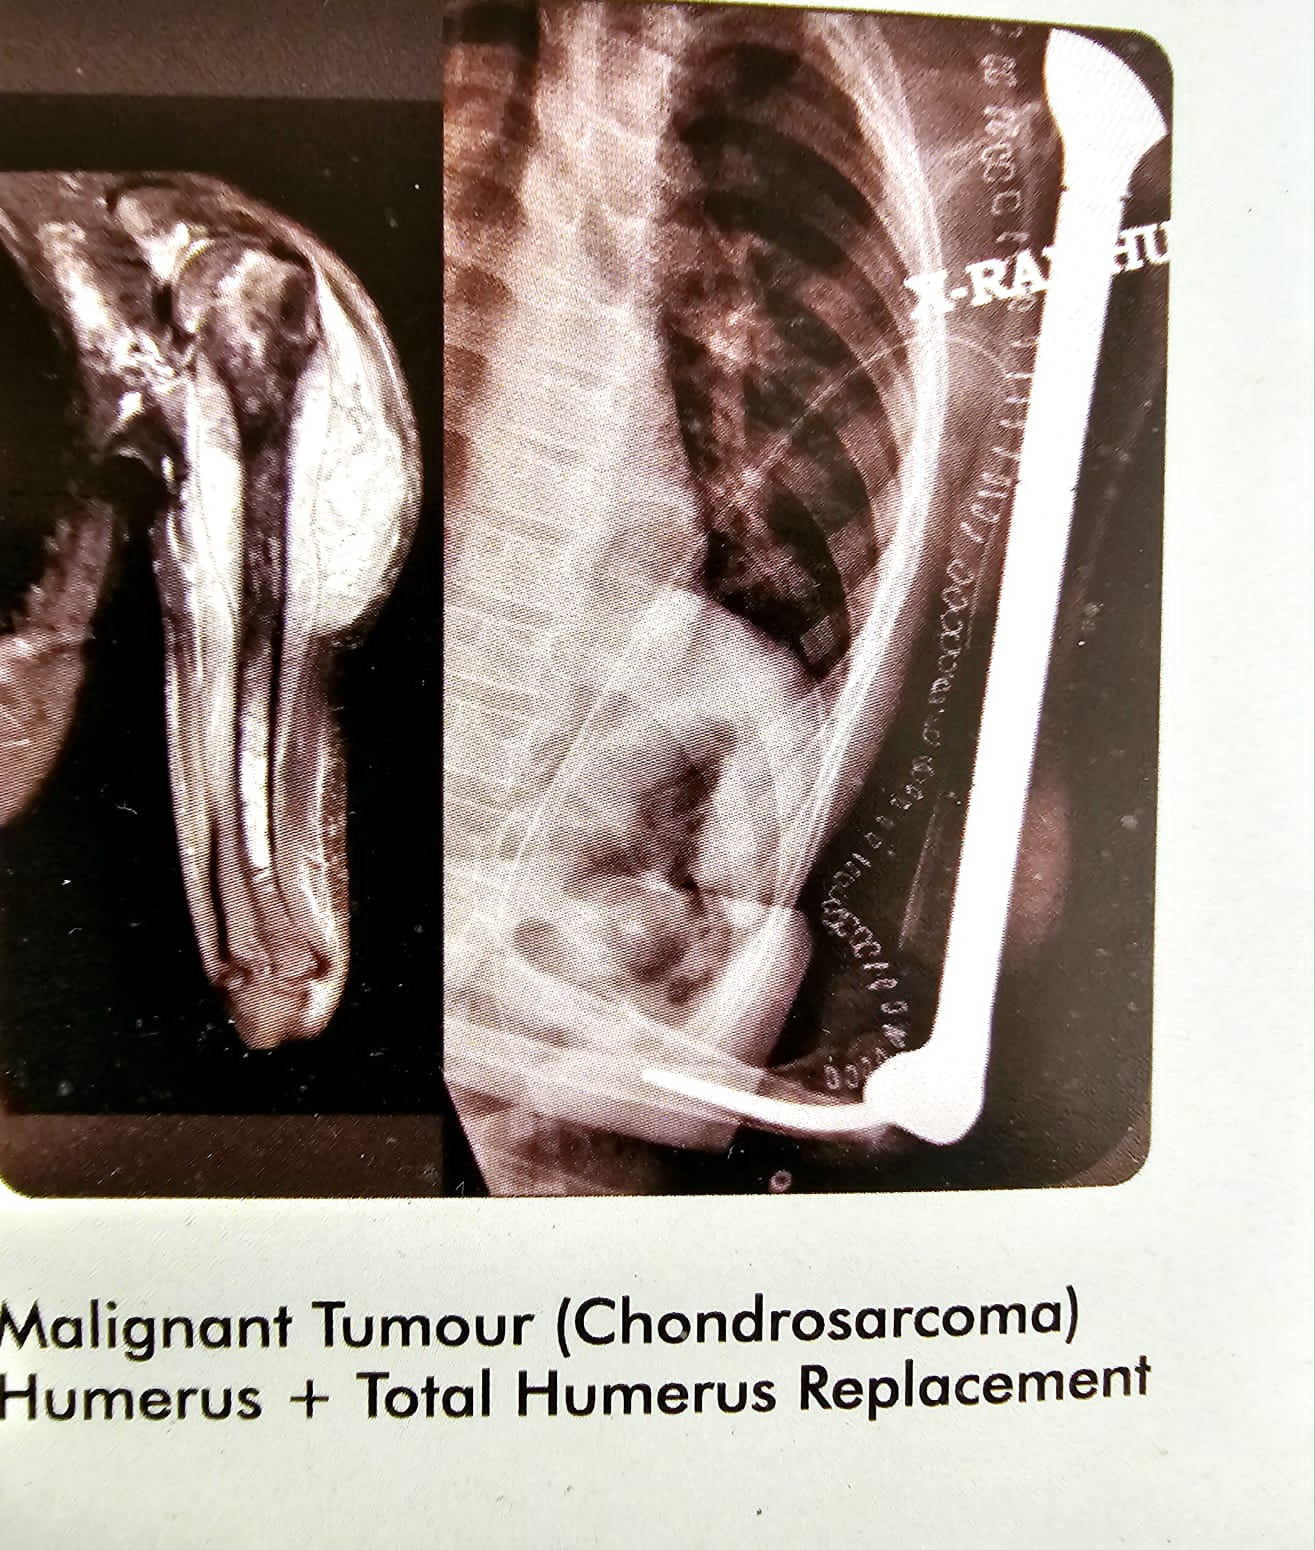

Malignant tumour (chondrosarcoma)

This is the case of malignant tumour chondrosarcoma of the humeral head and the proximal humeras in a seventeen year old boy from Nigeria. I replaced his entire humeras including the humeral head and also gave him an elbow. You can say a total humeral replacement with an elbow. Patient did very well, and continued to live for almost a year after the surgery, after that he succumbed to the malignant.

Malignant tumour (chondrosarcoma)

This is the case of malignant tumour chondrosarcoma of the humeral head and the proximal humeras in a seventeen year old boy from Nigeria. I replaced his entire humeras including the humeral head and also gave him an elbow. You can say a total humeral replacement with an elbow. Patient did very well, and continued to live for almost a year after the surgery, after that he succumbed to the malignant.